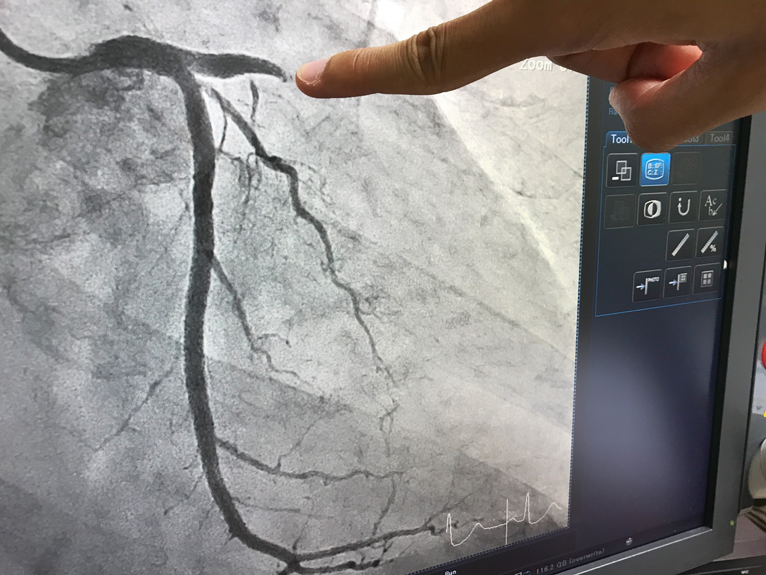

בעקבות העלייה בתוחלת החיים מתפתחת אוכלוסייה גדלה והולכת של חולים הסובלים מתעוקת חזה עמידה לטיפול. חולים אלה הם לרוב עם מחלה כלילית חסימתית מפושטת, לעיתים לאחר ניתוח מעקפים וצנתורים מרובים, אשר אינם מועמדים להתערבות נוספת

מנתונים שנאספו באירופה וארה"ב אנו למדים כי ביותר מ– 8% מבין המטופלים אשר מופנים לצנתור לב בגלל תעוקת חזה, אין אפשרות לטפל על ידי צנתור טיפולי או ניתוח מעקפים

פתיחת העורקים החסומים בלב על ידי צנתור טיפולי או על ידי ניתוח מעקפים יעיל בהפגת תעוקת החזה רק בכ– 75% מהמקרים. רבים מהסובלים מתעוקת חזה עברו בעבר צנתורי לב, או ניתוח מעקפים, ולמרות זאת ממשיכים לסבול מתעוקת חזה